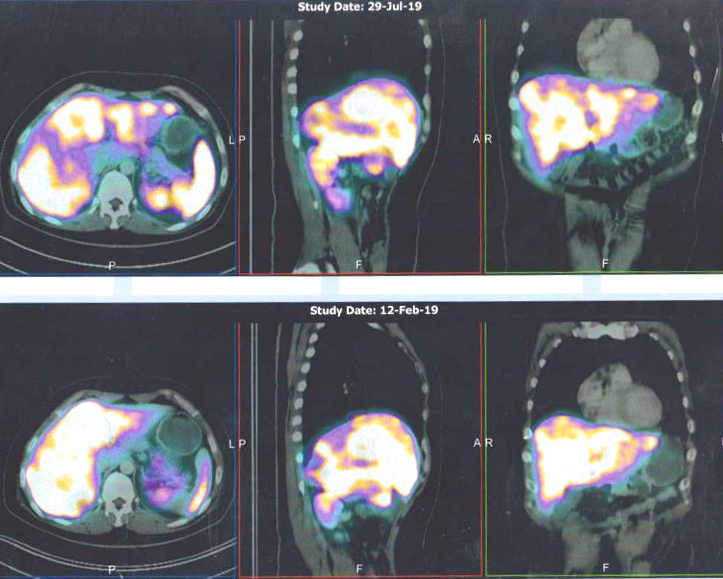

Let us look at the results of his PET scan.

Comparison of scan results: 29 July 2019 (top row) vs 12 February 2019 (bottom row)